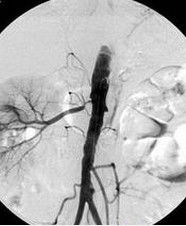

2.確診檢查篩選檢查陽性或雖陰性但臨床上高度懷疑者,可做經皮腎動脈造影術。腎動脈造影對腎動脈狹窄診斷最有價值,是診斷腎血管疾病的“金指標”可反映腎動脈狹窄的部位、範圍程度、病變性質、遠端分支及側支循環情況,並可觀查腎臟形態和功能改變以及對血管擴張或手術指征的判斷。